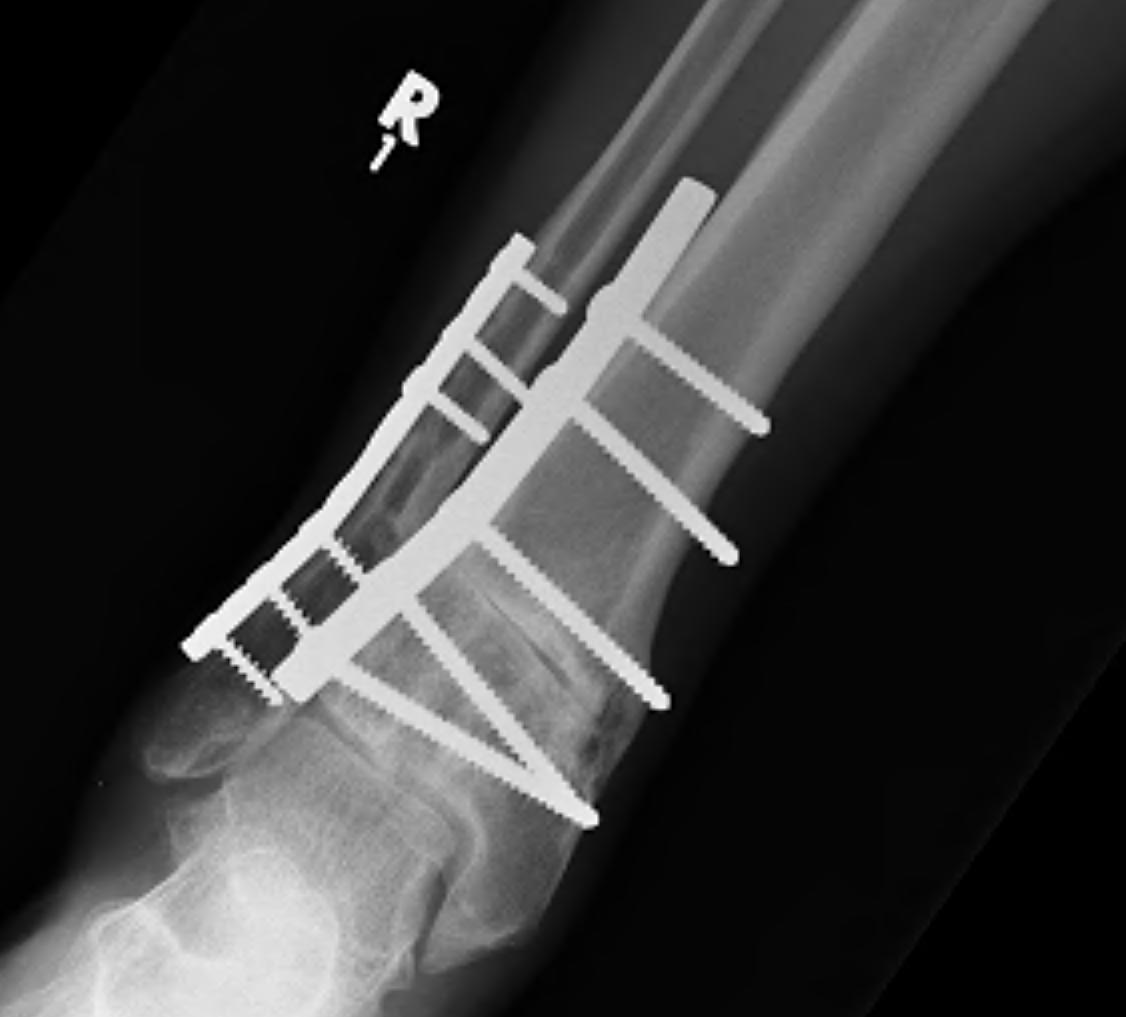

Tibial Plafond Pre External Fixator APTibial Plafond Pre External Fixator LateralTibial Plafond Post External Fixator APTibial Plafond Post External Fixator Lateral

Technique of ankle bridging delta frame

- two pins in the tibia away from surgical site

- transcalcaneal threaded pin placed medial to lateral

- pin in base of first metatarsal to keep foot in neutral position and prevent equinus contracture

- note: pin in base of first metatarsal places deep plantar branch of dorsalis pedis at risk